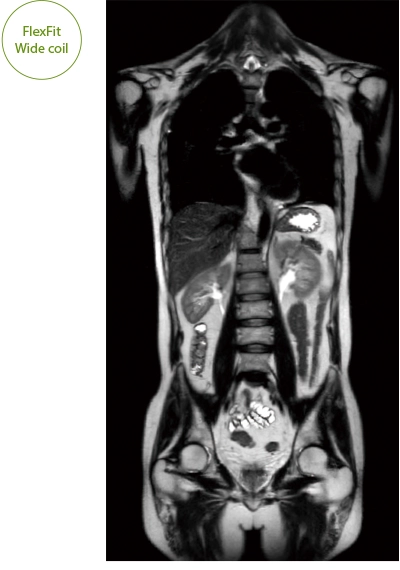

IP-RAPID x DLR Plus can be used for basic imaging such as VolumeScan, RadialScan, HalfScan, and many other imaging methods such as MultiContrastScan FatSep and DWI.

It can also be used with time-consuming scans such as Whole Body DWI and Whole Spine imaging, providing more detailed information in many areas than previously possible.